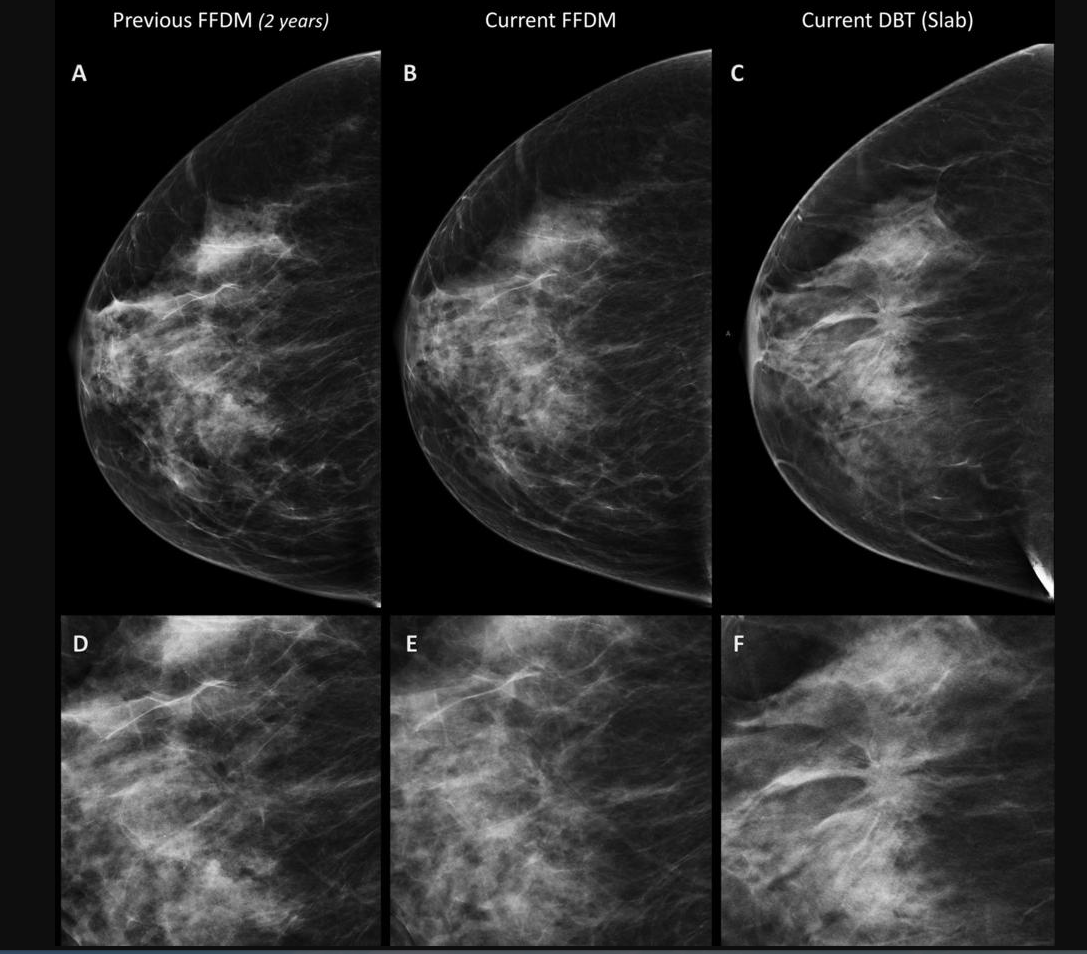

Unfortunately, he had to wait almost 15 years for the development of digital detectors and computers powerful enough to enable breast imaging using tomosynthesis. Exposure menu selection window page number displayed in conjunction with the chapter number. A mammogram provides an x-ray image of the breast. Tomosynthesis takes multiple pictures from several angles: 11 images during a 7-second exam. It highlights suspicious masses more clearly, allowing radiologists to effectively pinpoint the size, shape, and location of possible abnormalities.

Bagpiper breast center tomosynthesis experience piper knocker center was dignified to begin oblation tomosynthesis in the summer of 2014 this includes i unit at abbott northwestern and 1 at west wellness both sites utilzize selenia dimensions units just in case you were active to complain active the lack of original photos, one took . The X ray source was sick horizontally along the image. It's often referred to as multidimensional mammography because information technology provides advanced bosom imaging using A low-dose x-ray organisation and computer Reconstruction to create 3-dimensional breast images. Unlike prior-gen-eration mammography systems, which generate 2-dimensional images, breast tomosynthesis produces 3-dimensional images that are intended to reveal the inmost architecture of the breast, free from the distortio. Digital mammographic systems make tit tomosynthesis possible. Digital bosom tomosynthesis is sometimes called 3-d mammogram.

Quasi to digital mammography, tomosynthesis has been described as the next generation of digital screening. Breast tomosynthesis converts digital images into a spate of very vaporous layers or slices, building what is essentially a 3-d mammogram. Tomosynthesis, making the invisible visible. Efficiency-enhancing visu-alization tools will glucinium of particular grandness if tomosynthesis-generated images are to glucinium routinely used stylish the screening environment. Tomosynthesis, which is A medical term conceived by combining the terms tomography and synthesis, is letter a technology used to create coronal department images from letter a series of X ray images. Breast tomosynthesis takes many images of the entire titty.